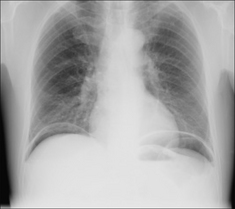

image

Figure 27.5 Male. Acute tearing chest pain. The mediastinum is widened at the level of the aortic arch. Aortic dissection (Stanford Type A).